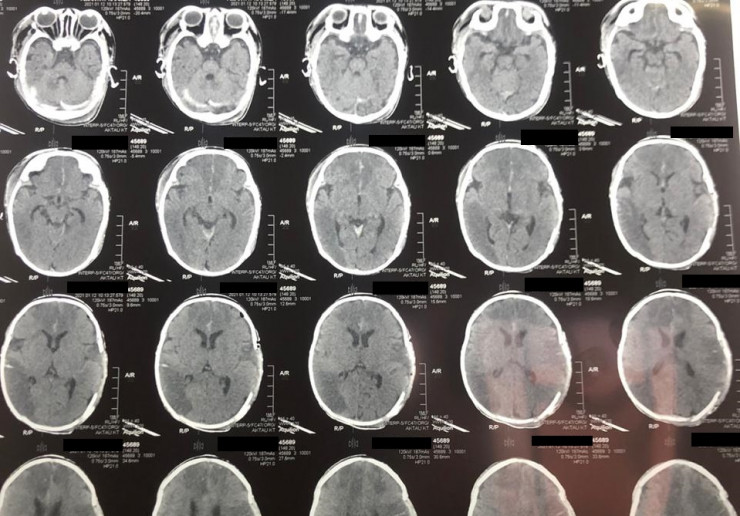

У младенца случился инсульт в Мангистауской области. Ребенка с диагнозом "острое нарушение мозгового кровообращения" (инсульт новорожденных) доставили в Мангистаускую областную многопрофильную детскую больницу 9 января, передает Tengrinews.kz со ссылкой на "Лада".

Как сообщили в больнице, у двухмесячного младенца из-за инсульта зафиксировали отек головного мозга, дислокационный синдром и кому I-II степени. Благодаря усилиям врачей 10 января состояние ребенка удалось стабилизировать. В экстренном порядке ему провели операцию по трепанации черепа, которая продлилась два часа.

"Такие случаи редко заканчиваются положительным результатом, но нам удалось спасти ребенка. В настоящий момент пациента перевели в отделение травматологии, он находится в среднетяжелом состоянии", - сообщил детский нейрохирург Ербол Кенжевалов.